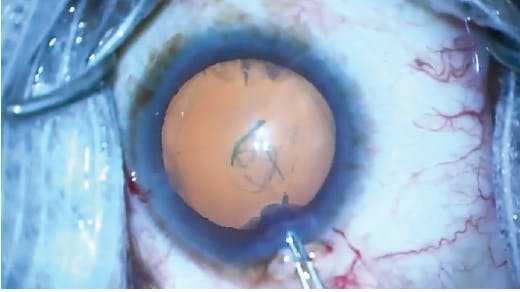

The patient underwent nasal Trabectome goniotomy combined with two-incision 360° ECP in June 2013 (Figure 2). From postoperative day 1 to year 4, the patient’s IOP was consistently in the 10 to 14 mm Hg range on latanoprost and dorzolamide-timolol. Even more important, his postoperative VFs remained stable on the four tests obtained up to 2017 (Figure 3). At that point, the patient moved and was lost to my follow-up care.

Figure 2. Trabectome goniotomy (A) was combined with two-incision 360° ECP (B) to minimize the patient’s risk of complications.